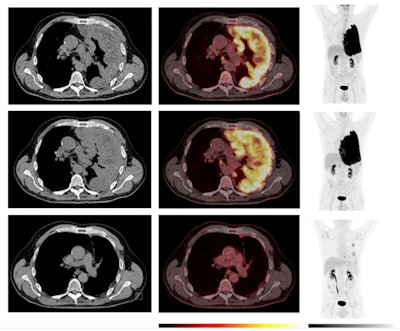

Example of a patient with a pseudoprogression. An initial increase in tumor volume and MTV and a decline in F-18 FDG uptake at week five was followed by a long-term objective tumor response/disease control. Comparative imaging from baseline (top row), week five (middle row), and year one (bottom row). To the left, axial CT images; in the middle, axial PET/CT images; and to the right, the MIP. The PET images are observed within a 0-10 SUV window. The patient was classified as having progressive disease at the first CT response assessment, before developing stable disease at week 12 and partial response at the week 18 CT scan according to mRECIST and immune RECIST. At week five, the PET/CT showed an increase in MTV, while F-18 FDG uptake (SUVmax and SUVpeak) has started to decline. At the one-year follow-up PET/CT, there is a notable change, with a visible reduction in tumor size, MTV, and F-18 FDG uptake. This corresponded with clinical performance status, which was reduced at week five and improved from week 12 and onwards. The patient died due to disease progression two years after the start of the treatment.